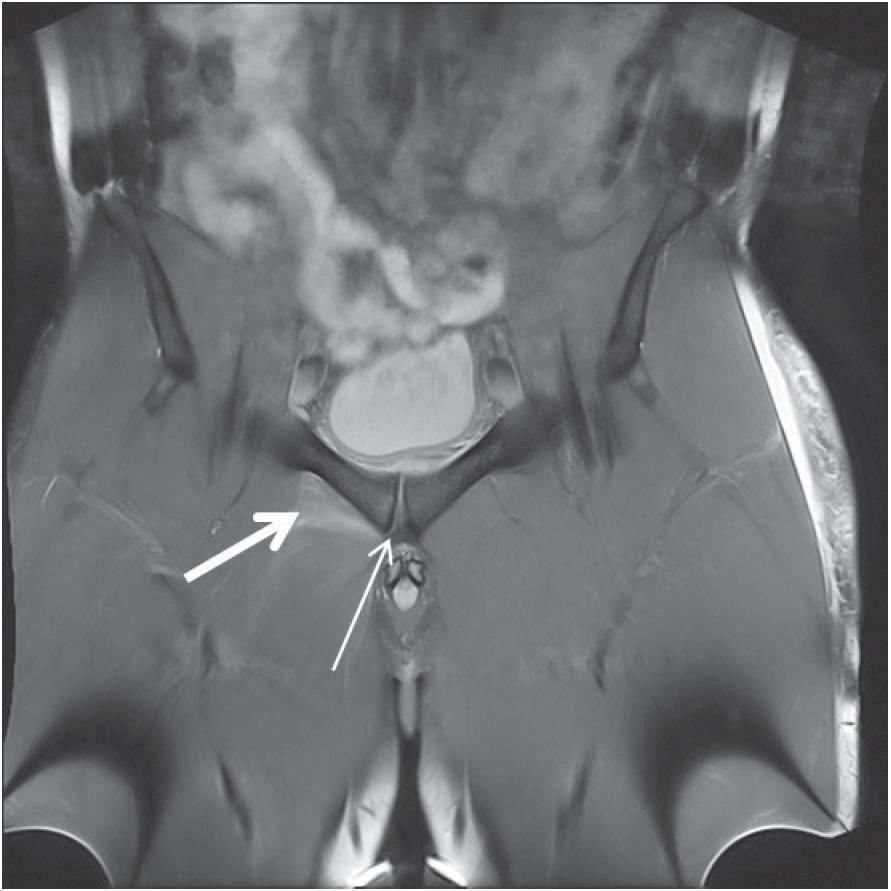

MRI classification of Morel-Lavallee lesions according to Mellado-Bencardino12

| Lesion type | T1W | T2W | Morphology | Other |

|---|---|---|---|---|

| Type 1 - Seroma | Homogenously hypointense seroma | Hyperintense collection | Laminar | No evidence of outer capsule formation |

| Type 2 – Subacute hematoma | Homogenously hyperintense | Homogenously hyperintense | Oval | Presence Thin capsule of methaemoglobin formation |

| Type 3 – Chronic organizing hematoma | Hypointense | Heterogeneous hypointense/ isointense | Oval | Thick capsule formation Capsular and internal enhacement on postcontrast sequences |

| Type 4-Closed laceration | Hypointense | Hyperintense | Linear | No capsule formation |

| Type pseudonodular 5-Small, rounded appearance | Variable | Variable | Round | Variable capsule formation |

| Type 6-Superimposed infection | Variable | Variable | Variable sinus tract | Thick enhancing capsule |